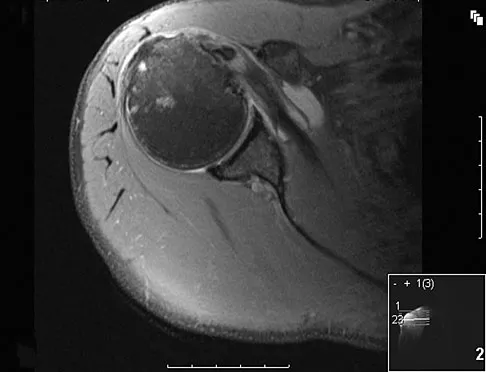

A professional baseball player has had intermittent, mild shoulder pain for the past 2 years. Nonsurgical management has consisted of anti-inflammatory drugs. Examination reveals atrophy of the infraspinatus muscle but not the supraspinatus. There is weakness in external rotation with the arm at his side but not at 90 degrees of abduction. He has no weakness or pain with resisted abduction. Electromyography confirms an isolated lesion of the suprascapular nerve branch to the infraspinatus. He is otherwise neurologically intact. An MRI scan of the shoulder shows no cysts but confirms atrophy of the infraspinatus muscle. What is the next most appropriate step in management?

Explanation

Suprascapular nerve injuries are more commonly seen in athletes who participate in overhead activities. When a patient is evaluated for posterior shoulder pain and infraspinatus muscle weakness or atrophy, electrodiagnostic studies are an essential part of the evaluation. In addition, imaging studies are indicated to exclude other diagnoses that can mimic a suprascapular nerve injury. Initial management should consist of cessation of the aggravating activity along with an organized shoulder rehabilitation program. If nonsurgical management fails to provide relief within 6 months to 1 year, surgical exploration of the suprascapular nerve should be considered. Release of the spinoglenoid ligament with resultant suprascapular nerve decompression may result in pain relief and a return of normal shoulder function. In this patient, who has a chronic neuropathy and mild symptoms, surgery is indicated only if nonsurgical management fails to provide relief and he is unable to perform at his position. Cummins CA, Bowen M, Anderson K, et al: Suprascapular nerve entrapment at the spinoglenoid notch in a professional baseball pitcher. Am J Sports Med 1999;27:810-812. Cummins CA, Messer TM, Nuber GW: Suprascapular nerve entrapment. J Bone Joint Surg Am 2000;82:415-424.